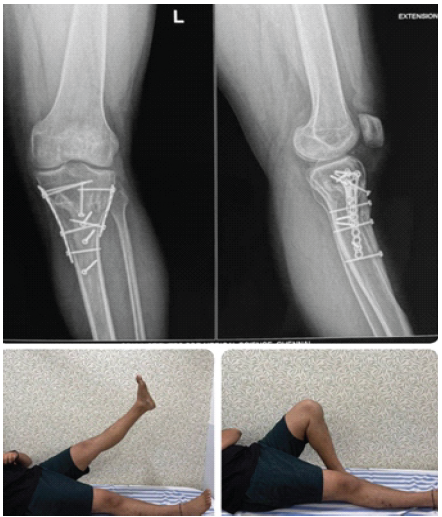

Figure 6: Post-operative clinical photographs demonstrating functional outcomes at 5 months.

In Fig. 6, the fixation appears stable in both anteroposterior and lateral views, showing appropriate alignment. The lower photographs show the patient performing active knee and hip mobilization exercises as part of post-operative rehabilitation.